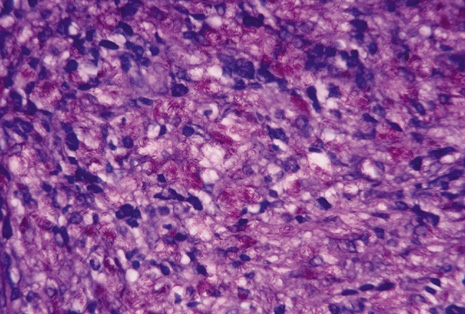

Many forms of uveitis are characterized by specific types of inflammatory cells. Usually, however, one encounters mixtures of cell types in any given specimen, with the relative percentages of lymphocytes and polymorphonuclear leukocytes varying. There may be unusual numbers of eosinophils, or macrophages laden with lens material may be present. Thus, an enumeration of the cells and a careful analysis of their structure can be useful as a diagnostic aid (Figs. 7, 8, 9, 10, 11, 12, 13, 14, 15, 16, 17, 18, 19, and 20). Figure 15 demonstrates eosinophils that were aspirated from the anterior chamber of a patient with Toxocara canis endophthalmitis. Figure 12 demonstrates malignant cell infiltrate from the vitreous, showing the stained presence of monoclonal light chains being elaborated in the cytoplasm. Interleukin-10, detectable in the vitreous of intraocular lymphoma patients, is also directly indicative of both the clinical activity and the number of malignant cells as observed by cytopathology.

Precise identification and culture of bacterial and fungal pathogens from both the aqueous humor and the vitreous fluid can be obtained. Gram's stain and Giemsa's stain smears of centrifuged specimens from the aqueous humor and the vitreous humor frequently demonstrate the bacterial or fungal causative agent. Attempts to isolate bacteria and fungi and to identify them on Gram's stain or Giemsa's stain smears have been most rewarding in the following cases: (a) postoperative endophthalmitis, (b) infection after a penetrating injury of the eye, (c) drug abuse patients with endogenous endophthalmitis (Figs. 21, 22, 23, 24, and 25), (d) patients receiving hyperalimentation, and (4) patients who are immunocompromised as a result of exogenous immunosuppressive agents.